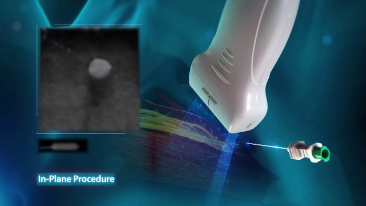

Assim como o n├Łvel de qualidade de imagem premium, o Resona 7 tamb├®m melhora as capacidades de investiga??o cl├Łnica com o revolucion├Īrio Fluxo V para avalia??o hemodin?mica vascular e a aquisi??o de plano mais inteligente do conjunto de dados 3D para diagn├│stico CNS fetal. Combinando a opera??o mais intuitiva baseada em gesto de multi-toques e todos os recursos cl├Łnicos essenciais, Resona 7 est├Ī realmente conduzindo novas ondas na inova??o de ultra-som.